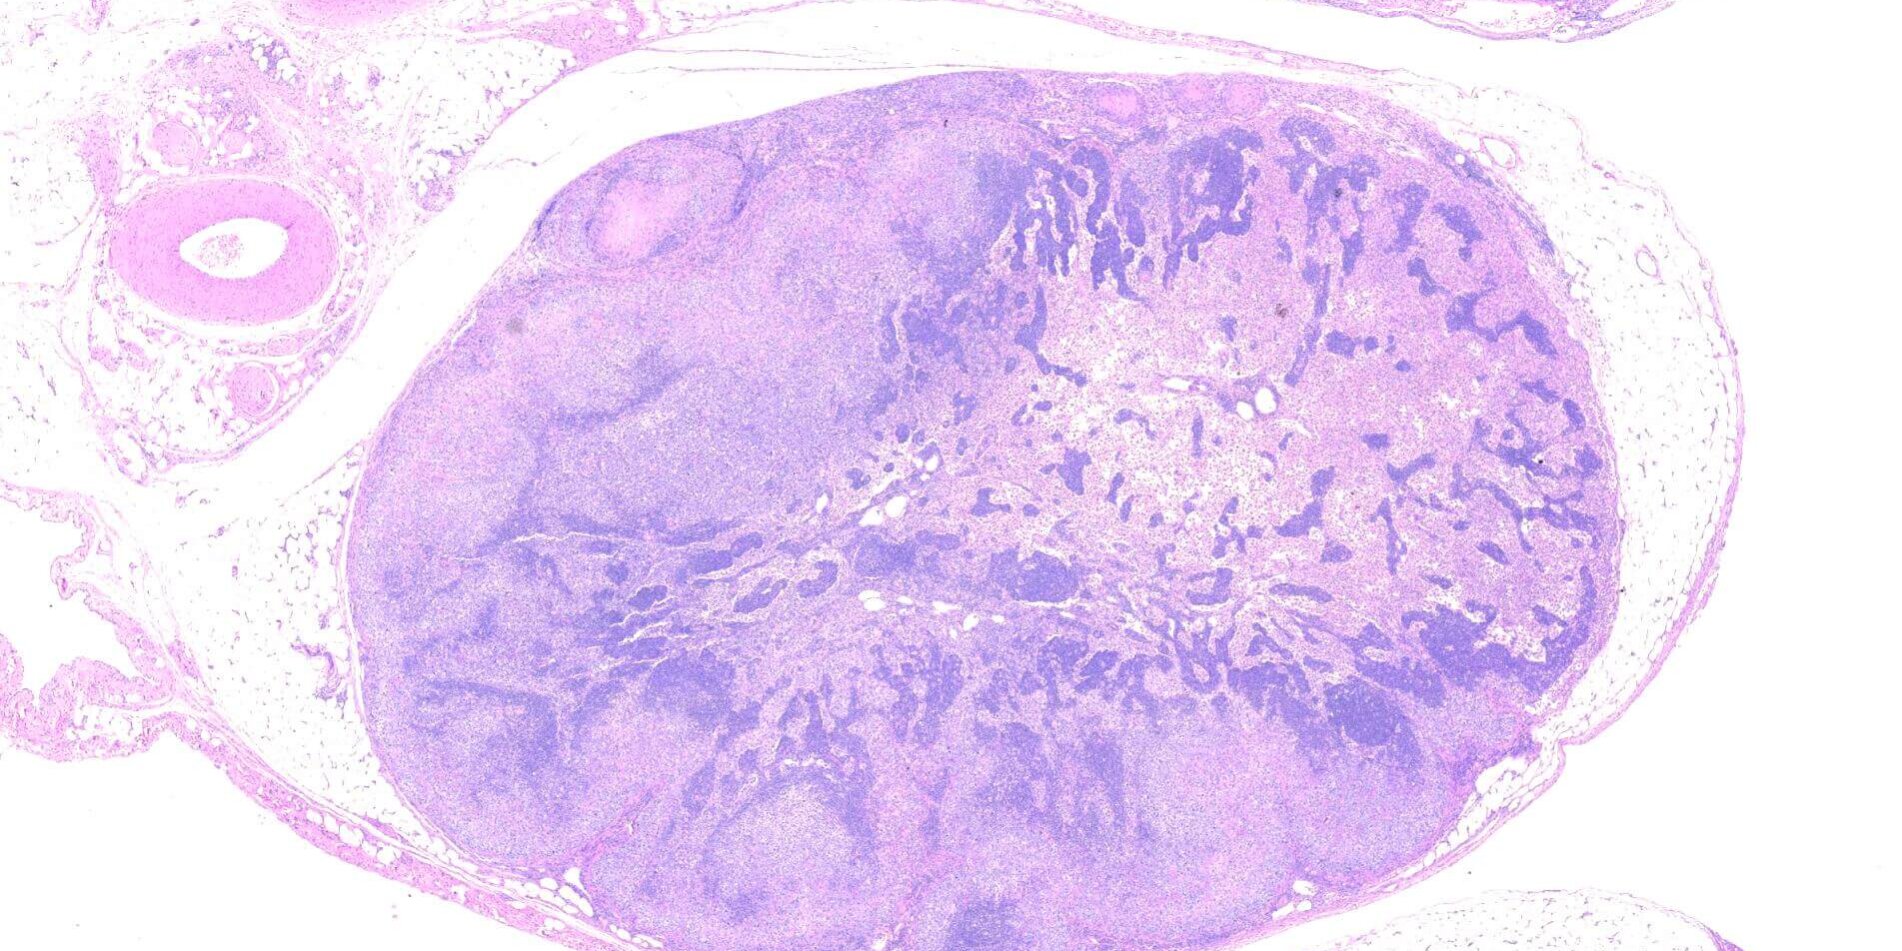

本次的病例是一隻年輕犬隻,臨床主訴是長期血痢、黏液便、眼盲,但精神食慾沒有明顯變化。開腹後有結腸增厚、多發臟器白點、結節生長。病理檢查發現結腸及腸繫膜淋巴結 有嚴重壞死,並且有大量不具染色性的物質堆積。因懷疑有黴菌或藻類感染的可能性,進行Peiodic-Acid Schiff (PAS)染色,結果顯示有大量帶有細胞壁 的橢圓形物質堆積,形態上符合原孢囊藻病。